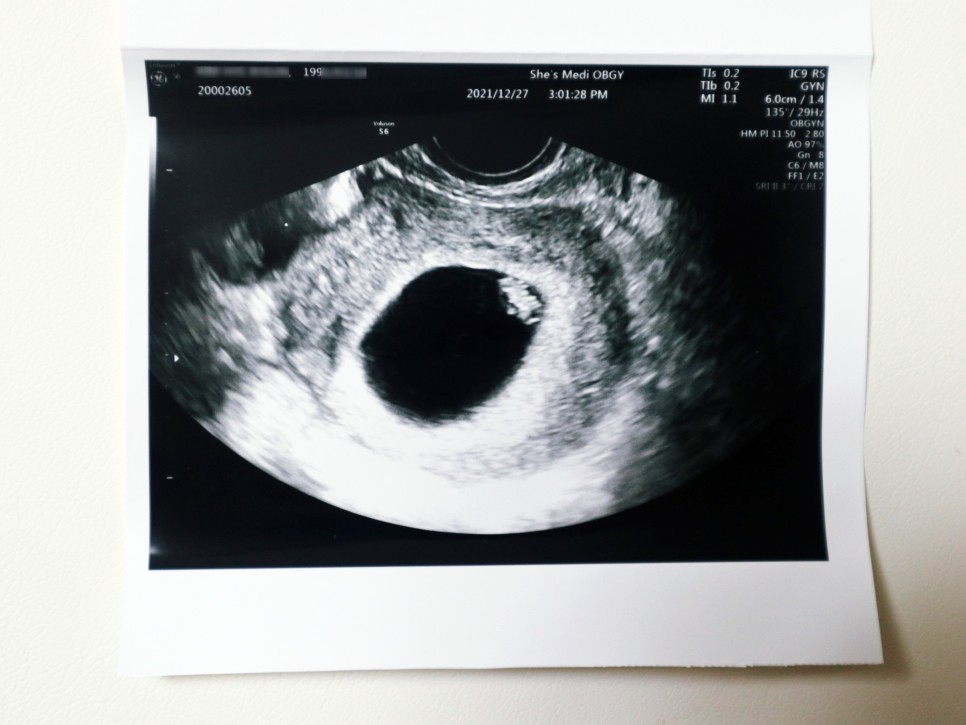

임신 7주 0일 (21년 12월 27일) 임신 7주차 태아심박동수 태아소견 신장 0.9cm

임신 4주 5일 첫 방문 때 0.2cm 짜리 아기 집을 봤는데 실제로 태아는 그걸 몰랐던 거예요.그래서 이날은 아기 집에 두 대를 확인하고 심박수를 체크하는 날이었어요.임신 7 주째, 초음파 상 아기 집도 엄청 커지고 있었는데, 그 속에서 젤리 곰의 아기를 발견할 수 있었습니다. 노른자도 꼭 확인했어요선생님이 보시기에 넓은곳이 많은데 저위에 붙어있대 ㅋㅋㅋ

임신 초기에 엽산과 비타민D를 자주 먹으라고 소량의 피눈물은 괜찮지만 생리혈처럼 쏟아지는 증상이 있으면 바로 내원하라고 했습니다.아기 심장박동기도 굿!!!